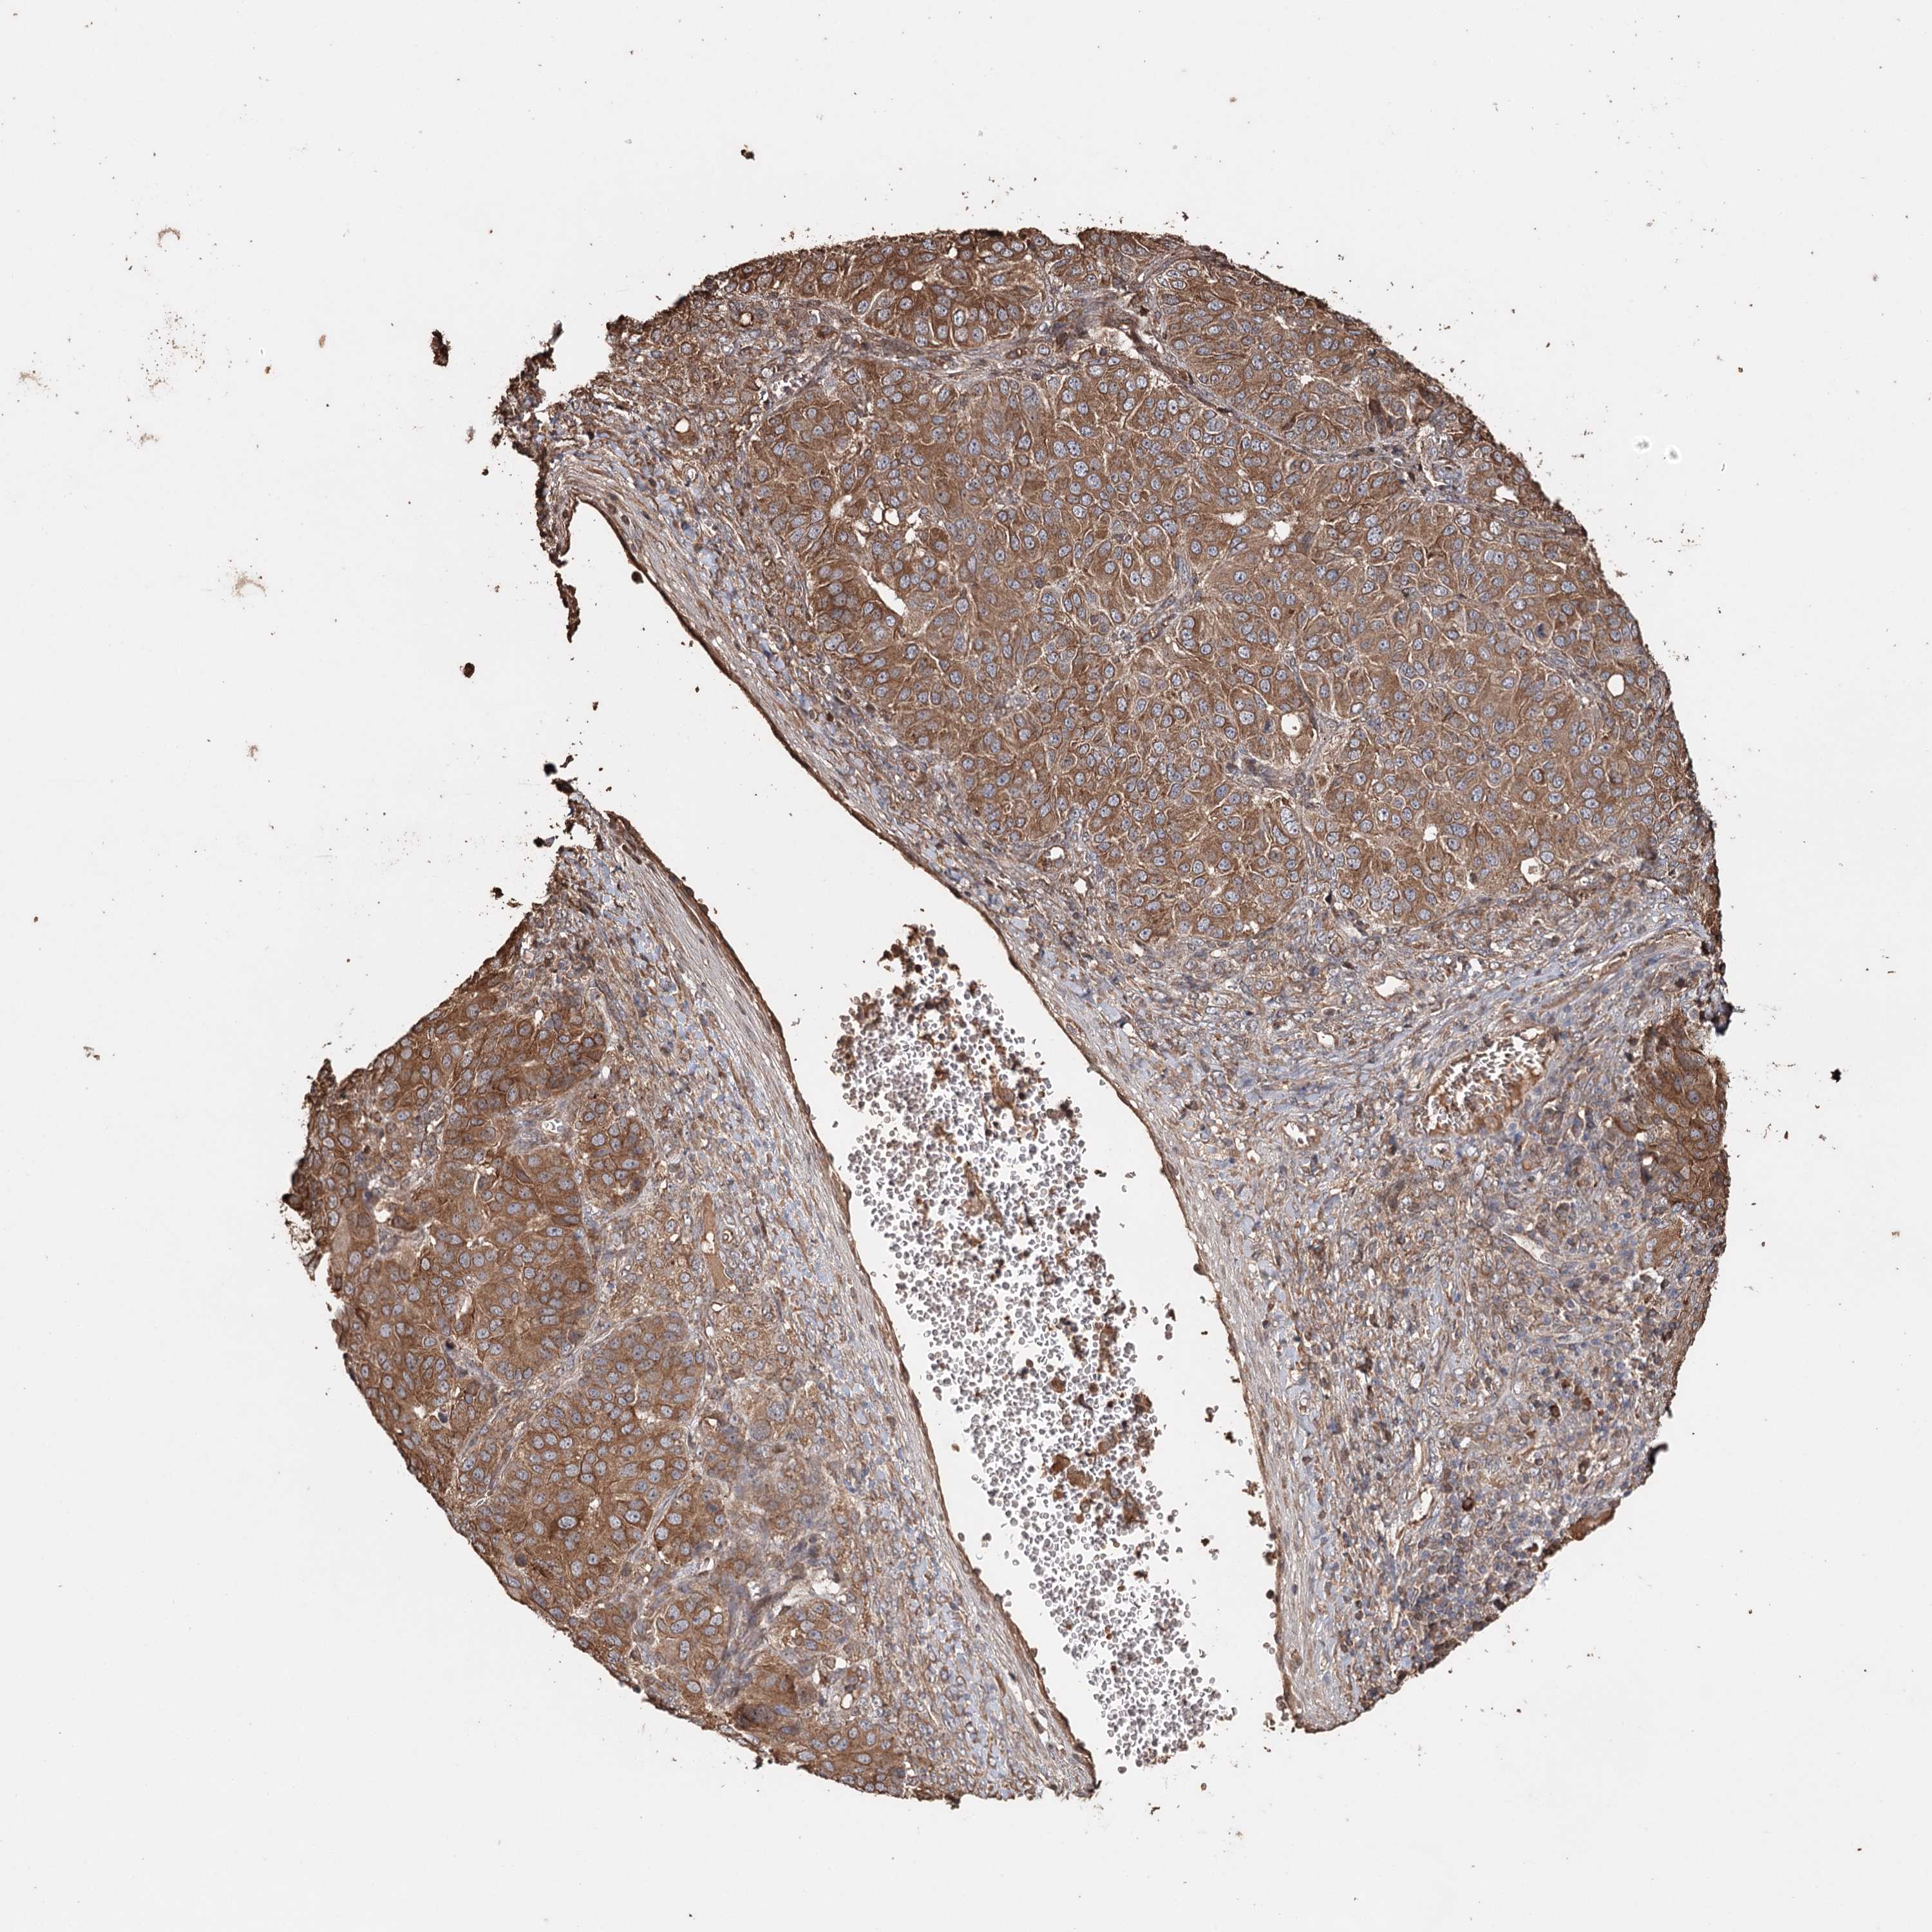

OVARIAN CANCER - Protein expressioni

A mouse-over function shows sample information and annotation data. Click on an image to view it in a full screen mode. Samples can be filtered based on level of antibody staining by selecting one or several of the following categories: high, medium, low and not detected. The assay and annotation is described here.

Note that samples used for immunohistochemistry by the Human Protein Atlas do not correspond to samples in the TCGA dataset.

Antibody stainingi

Antibody staining in the annotated cell types in the current human tissue is reported as not detected, low, medium, or high, based on conventional immunohistochemistry profiling in selected tissues. This score is based on the combination of the staining intensity and fraction of stained cells.

Each image is clickable and will lead to virtual microscopy that enables deeper exploration of all samples and also displays staining intensity scores, fraction scores and subcellular localization as well as patient and tissue information for each sample.

Antibody HPA005480

Staining

High

Medium

Low

Not detected

Cystadenocarcinoma, serous, NOS